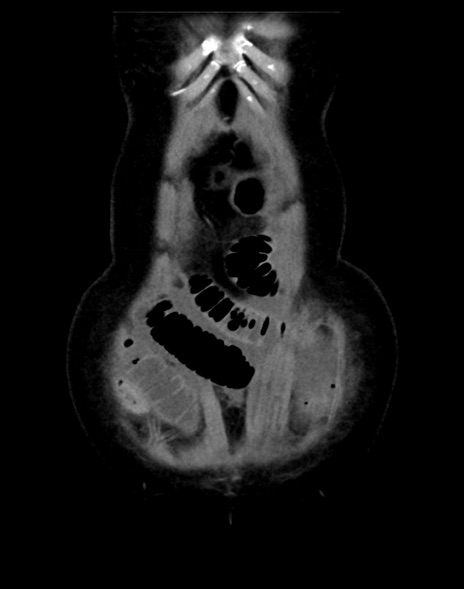

症例13 CT(冠状断像)1日半後